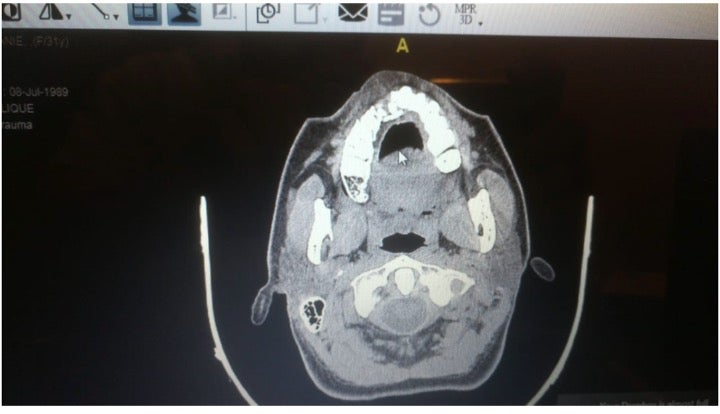

X-ray showing a fracture to a protesters’ maxillary bone after she was shot with a rubber ball.

© 2020 Private